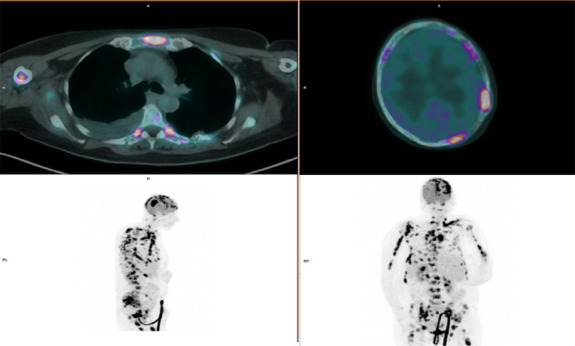

When "Myeloma" is not a Myeloma: a case report of malignant bone lymphoma.

Abstract Image